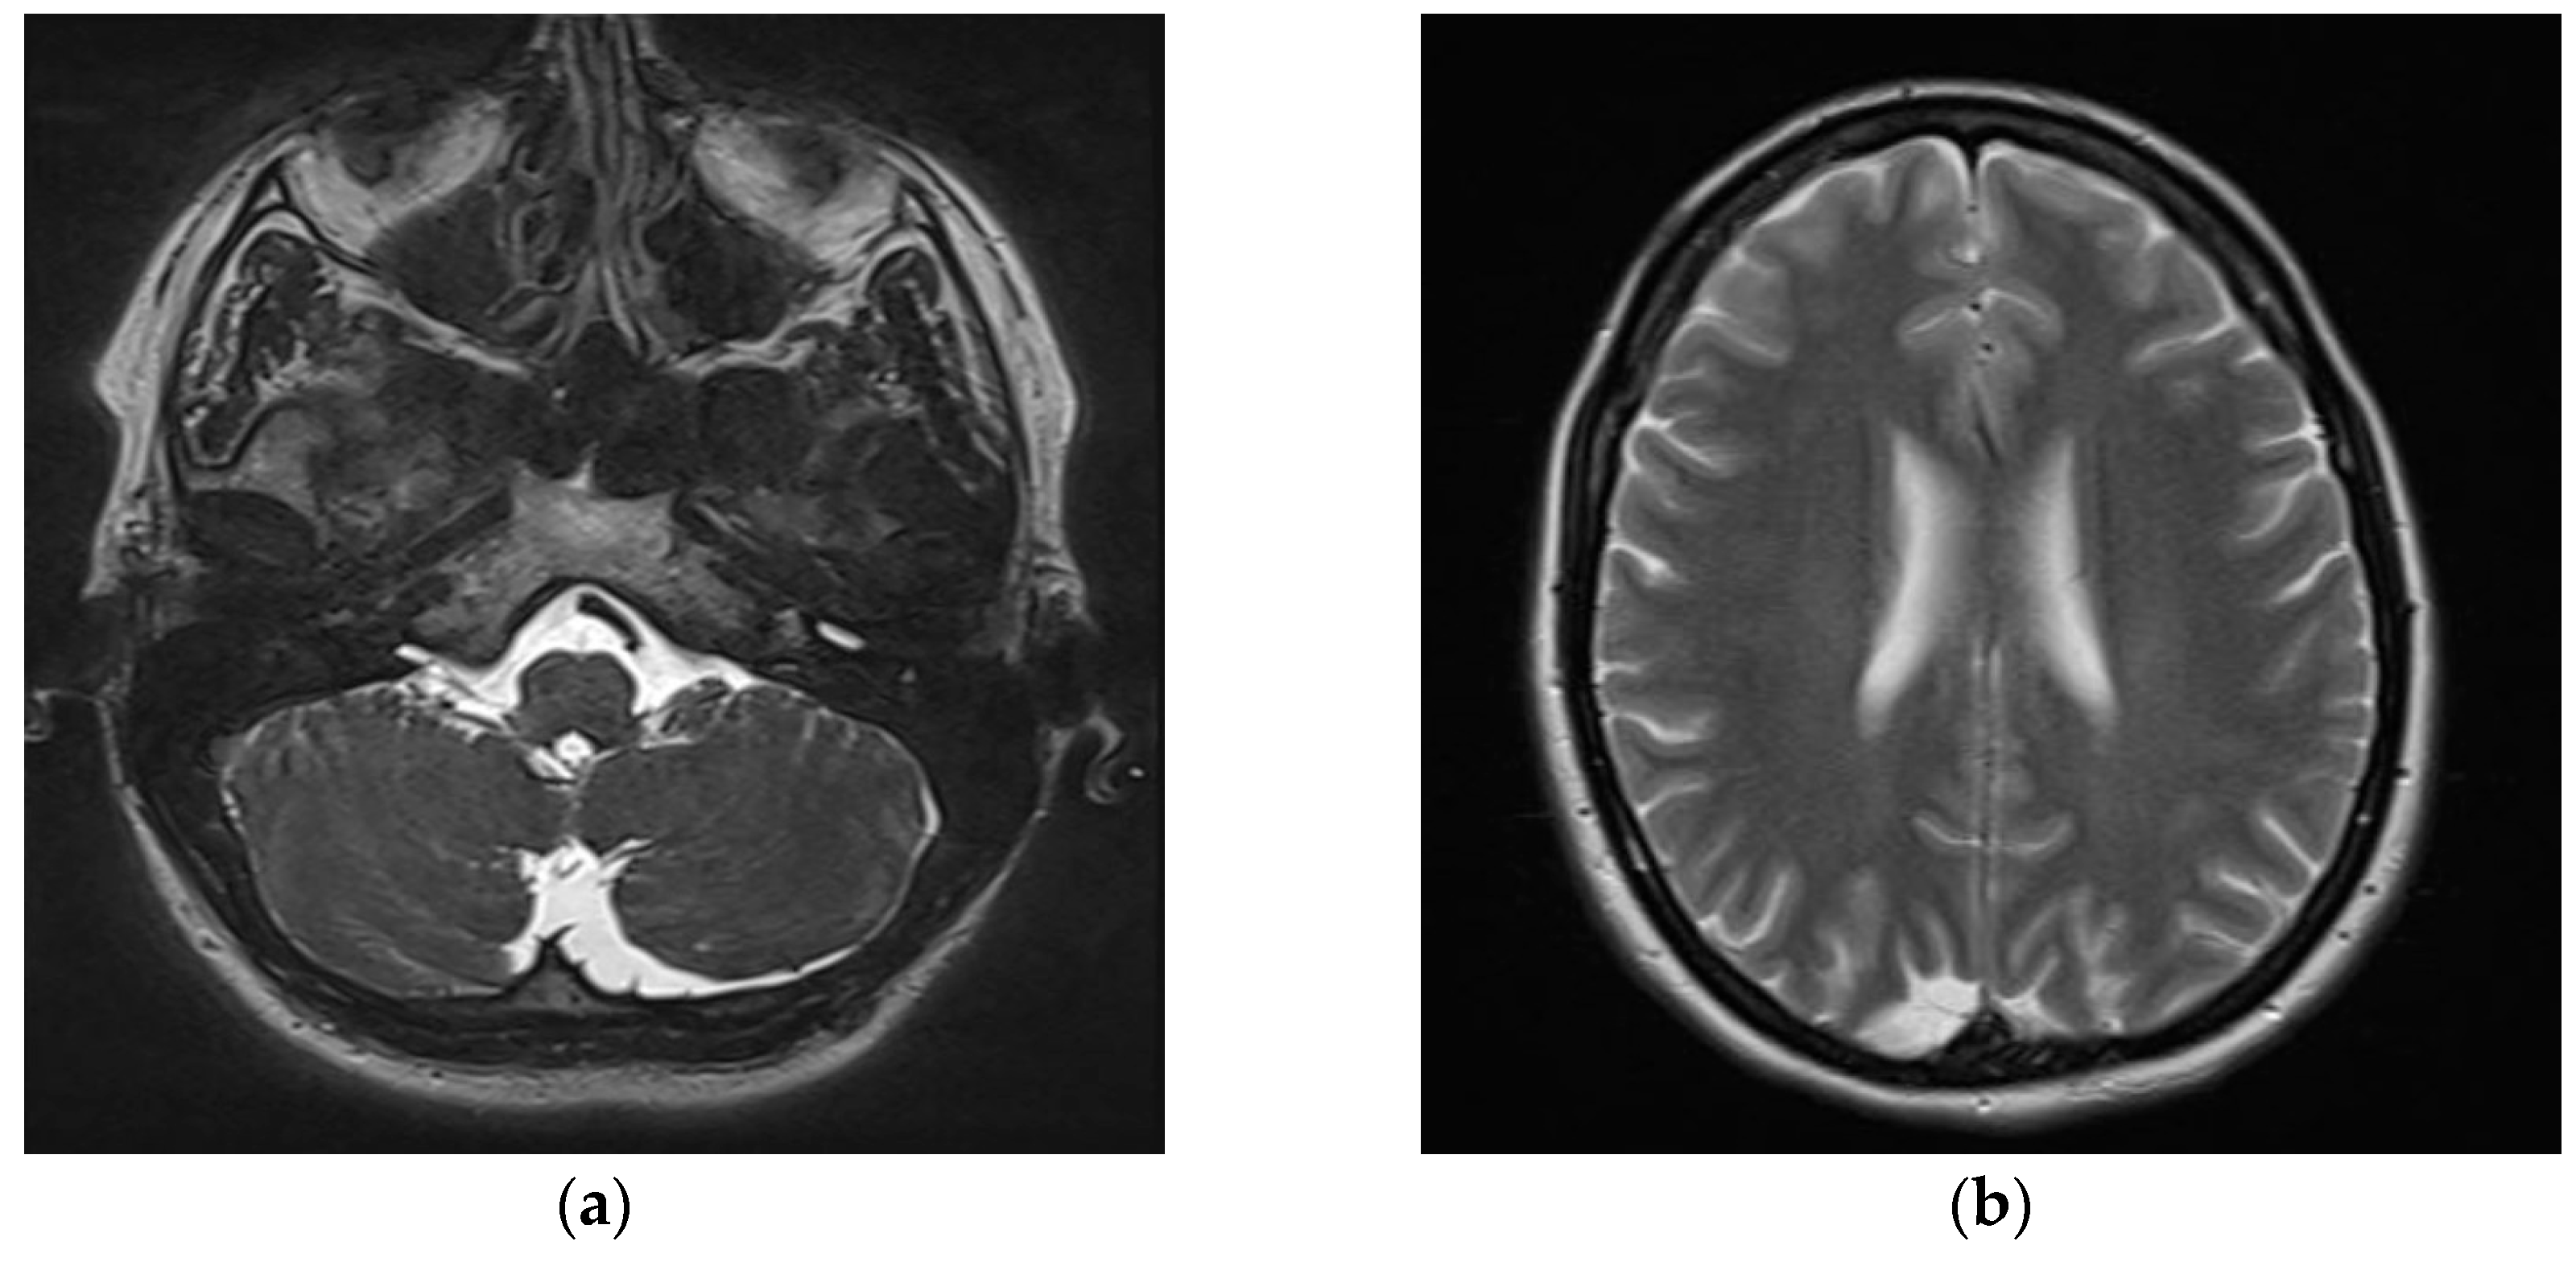

2. Detailed Case Presentation